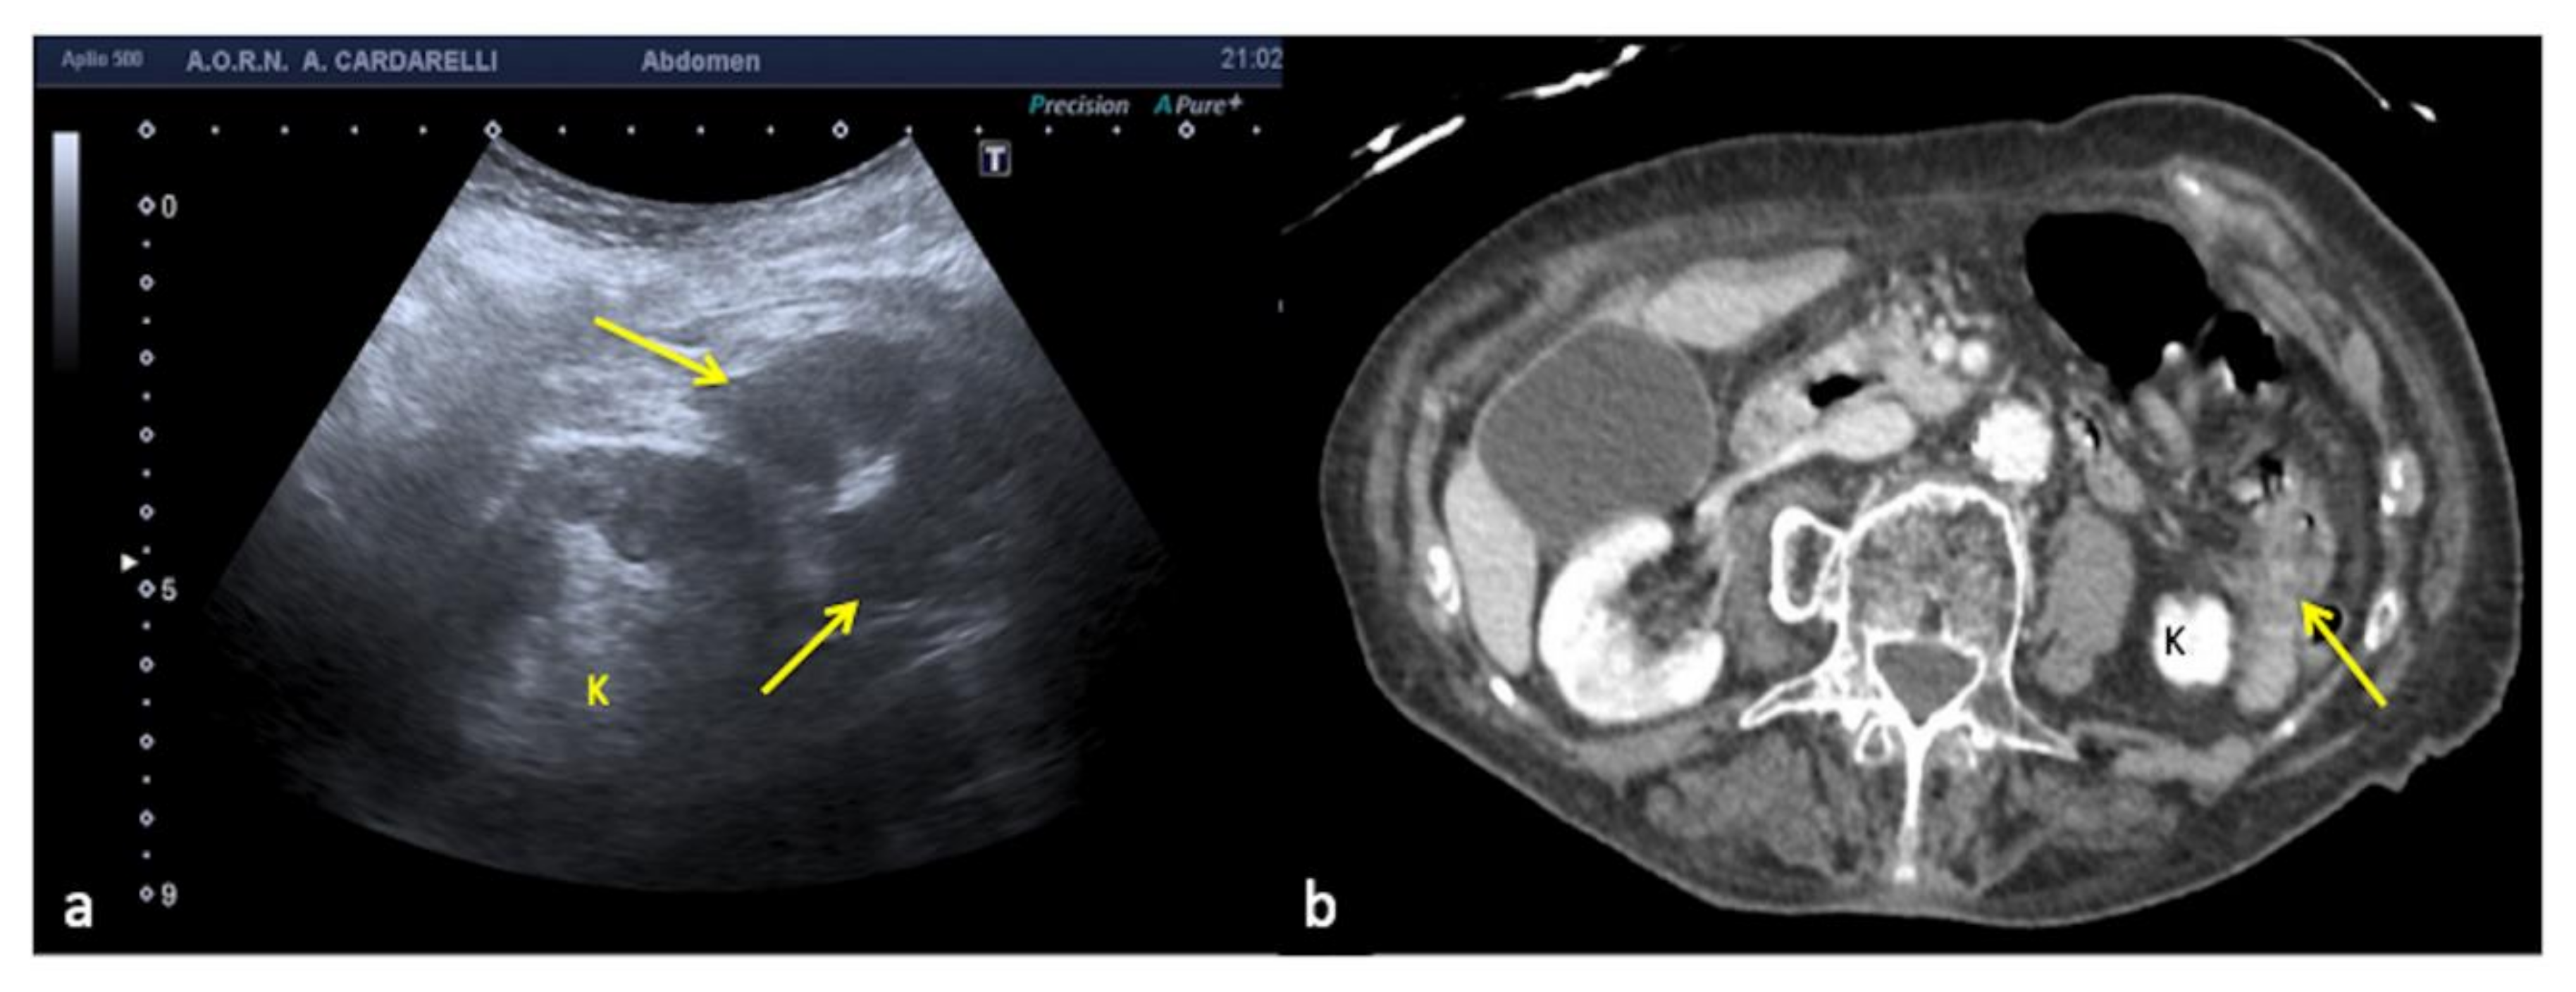

3.1.4. Refraction Artifacts